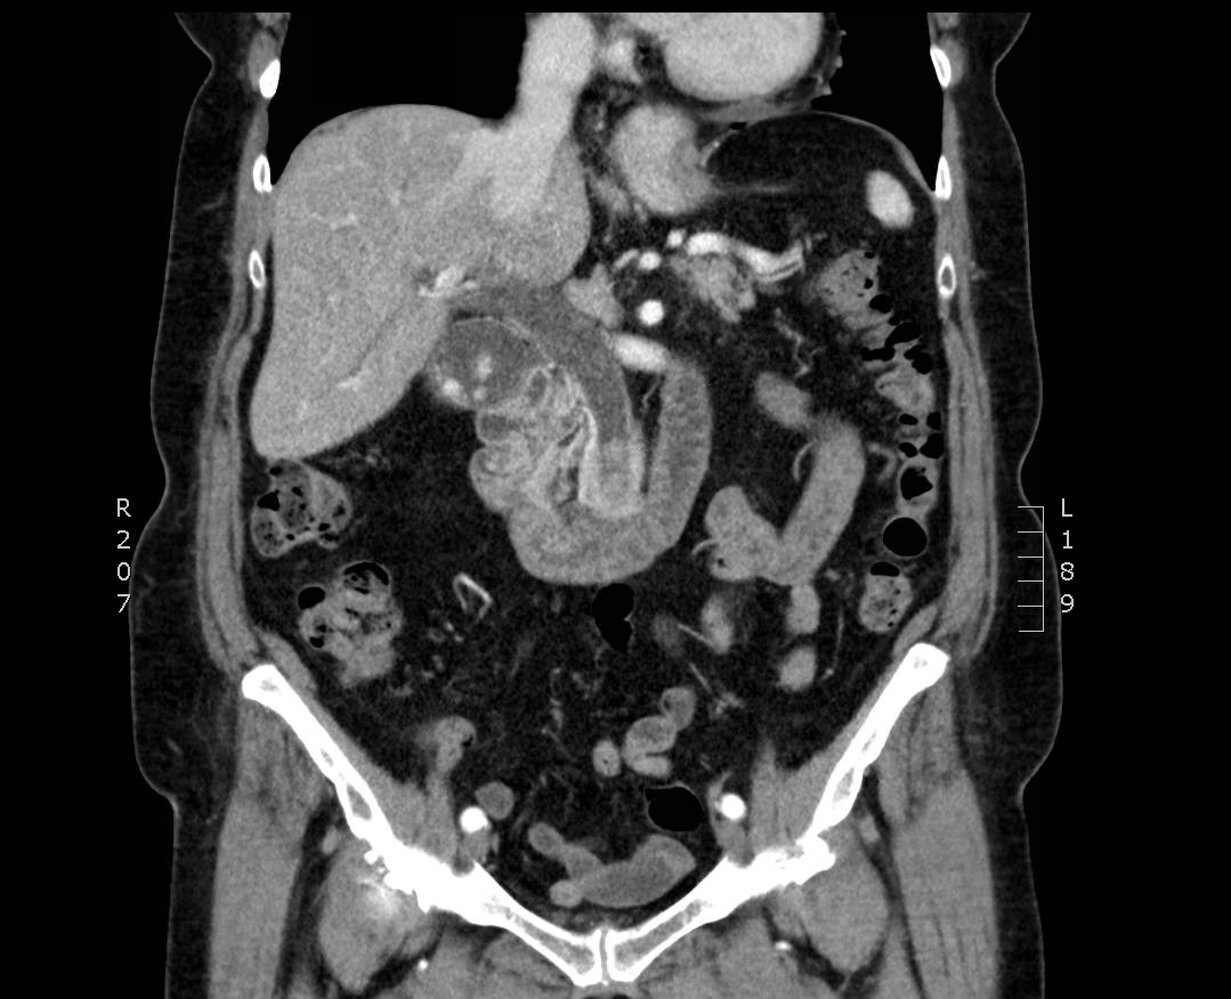

CT scan with IV contrast [11][12][13]

• Supportive findings [13]

• Concentric thickening and heterogeneous enhancement of the walls of the biliary tree [15]

• Bile duct dilation

• Periductal edema

• Evidence of underlying cause: choledocholithiasis, biliary tumor , biliary-enteric fistula, hydatid cyst, etc.

• Evidence of complications: pericholecystic or liver abscess, portal vein thrombosis.